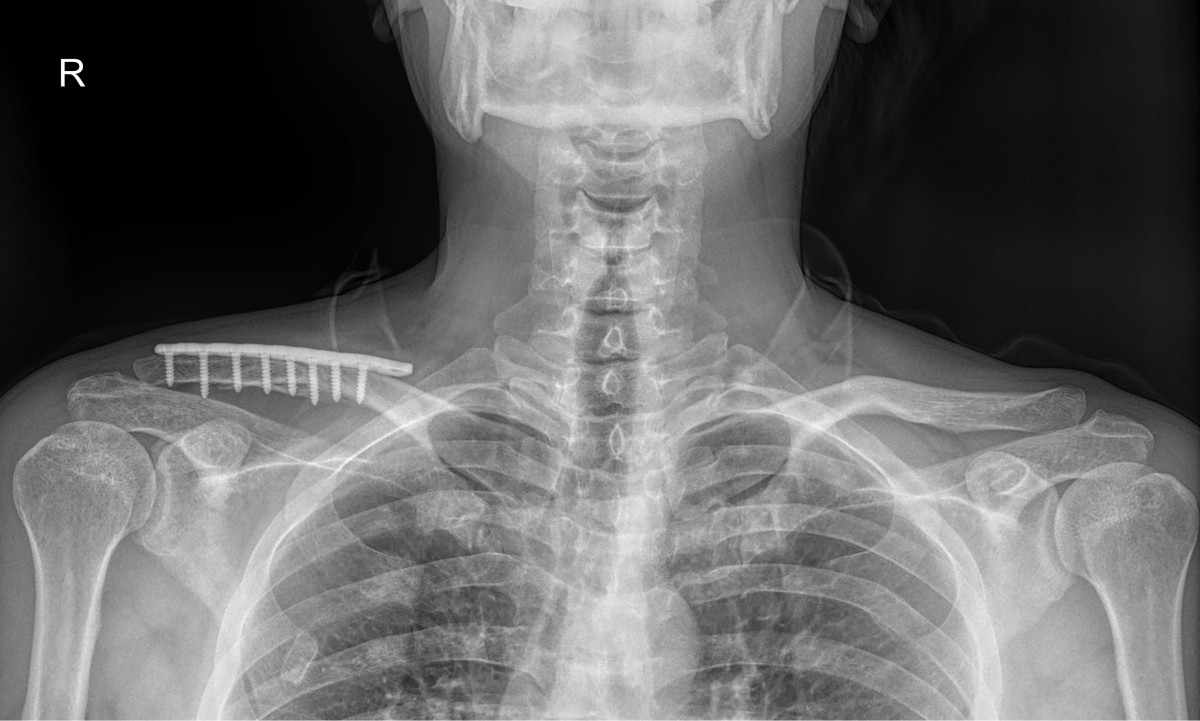

이재상원장님 어깨 골절 수술 박근O 환자

작성자 최고관리자 댓글 0건 조회 821회 작성일 25-09-16 14:54

dae765e4d9ac96aee867c9d6292d8784_1758002058_7436.jpg